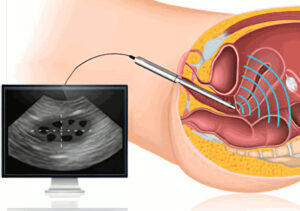

Διακολπικός υπέρηχος μήτρας ωοθηκών

Ο διακολπικός υπέρηχος των ωοθηκών είναι μια εξέταση που χρησιμοποιεί την υπερήχο για τον έλεγχο των ωοθηκών και της μήτρας. Αυτή η εξέταση είναι συχνά χρήσιμη για τη διάγνωση και την παρακολούθηση διαφόρων γυναικολογικών καταστάσεων. Είναι ειδικά σημαντική για γυναίκες που αντιμετωπίζουν προβλήματα σχετικά με την αντισύλληψη, την ανεπιθύμητη στειρότητα, ή άλλες γυναικολογικές διαταραχές.

Ο διακολπικός υπέρηχος των ωοθηκών είναι μια εξέταση που χρησιμοποιεί την υπερήχο για τον έλεγχο των ωοθηκών και της μήτρας. Αυτή η εξέταση είναι συχνά χρήσιμη για τη διάγνωση και την παρακολούθηση διαφόρων γυναικολογικών καταστάσεων. Είναι ειδικά σημαντική για γυναίκες που αντιμετωπίζουν προβλήματα σχετικά με την αντισύλληψη, την ανεπιθύμητη στειρότητα, ή άλλες γυναικολογικές διαταραχές.

Η εξέταση περιλαμβάνει τη χρήση ενός ειδικού αισθητήρα υπερήχων, ο οποίος τοποθετείται στο εσωτερικό του κόλπου. Αυτό επιτρέπει στον γιατρό να παρακολουθεί την κατάσταση των ωοθηκών και της μήτρας με πολύ υψηλή ευκρίνεια.

Ο διακολπικός υπέρηχος μπορεί να χρησιμοποιηθεί για τα εξής:

- Διάγνωση Προβλημάτων Ωοθηκών: Παρακολούθηση της ωοθηκικής δραστηριότητας και εντοπισμός προβλημάτων, όπως κύστεις ή όγκοι.

- Αντισύλληψη: Αξιολόγηση της ωοθηκικής δραστηριότητας και παρακολούθηση του ωοθηκικού κύκλου για τη βέλτιστη στιγμή σύλληψης.

- Παρακολούθηση Εγκυμοσύνης: Κατά τη διάρκεια της εγκυμοσύνης, ο διακολπικός υπέρηχος χρησιμοποιείται για την παρακολούθηση της ανάπτυξης του εμβρύου.

- Αξιολόγηση Γυναικολογικών Συμπτωμάτων: Εάν υπάρχουν γυναικολογικά συμπτώματα, όπως πόνος ή ανωμαλίες στον κύκλο της περιόδου, ο υπέρηχος μπορεί να βοηθήσει στον εντοπισμό των αιτίων.

Η εξέταση είναι συνήθως ανώδυνη και ασφαλής. Συστήνεται σε γυναίκες που αντιμετωπίζουν προβλήματα στην αναπαραγωγική υγεία ή που χρειάζονται παρακολούθηση για άλλους λόγους.

Υπερηχογραφικός κολπικός έλεγχος μήτρας και ωοθηκών

Ο υπερηχογραφικός κολπικός έλεγχος (transvaginal ultrasound) είναι μια διαγνωστική διαδικασία που χρησιμοποιεί έναν υπερήχο για να δημιουργήσει εικόνες του εσωτερικού του γυναικείου γεννητικού συστήματος, περιλαμβανομένης της μήτρας και των ωοθηκών. Ο υπερηχογραφικός κολπικός έλεγχος προσφέρει λεπτομερείς εικόνες και βοηθά στη διάγνωση και παρακολούθηση διαφόρων καταστάσεων.

Στη διάρκεια του υπερηχογραφικού κολπικού ελέγχου:

- Εφαρμόζεται ένας κενός πολυμερής αισθητήρας (υπερηχητική μετατροπέας) σε ένα ειδικό εισαγωγικό, το οποίο τοποθετείται στον κόλπο της γυναίκας.

- Ο αισθητήρας παράγει υπερήχους που διεισδύουν στα οργανικά ιστά της μήτρας και των ωοθηκών, δημιουργώντας εικόνες που εμφανίζονται σε οθόνη.

- Ο γιατρός ή ο υπερηχογραφικός τεχνίτης εξετάζει τις εικόνες για να αξιολογήσει τη δομή και τη λειτουργία της μήτρας, των ωοθηκών, και των γύρω ιστών.

Ο υπερηχογραφικός κολπικός έλεγχος χρησιμοποιείται για πολλούς σκοπούς, συμπεριλαμβανομένης της αξιολόγησης των ωοθηκών για ωοθηκική υπερστιμούλωση, τον έλεγχο της υγείας του εμβρύου κατά τη διάρκεια της εγκυμοσύνης, τον έλεγχο κύστεων και όγκων, καθώς και για τη διάγνωση γυναικολογικών παθήσεων.

Ο υπερηχογραφικός κολπικός έλεγχος είναι μια ασφαλής και μη επεμβατική διαδικασία, που συχνά επιτρέπει στους γιατρούς να αξιολογήσουν δομές και παθήσεις με πολλή λεπτομέρεια.